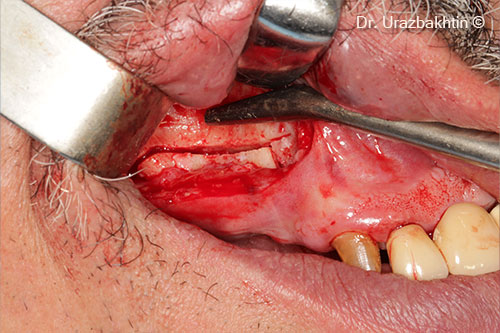

Tăng chiều cao xương hàm bằng kỹ thuật cắt xương ngang vùng hàm

Một bệnh nhân nam (77 tuổi) cần phẫu thuật nâng cao chiều dọc xương hàm.